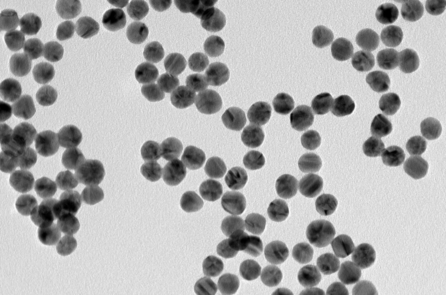

Cách tốt nhất để ngăn ngừa tái phát và các đợt đau khớp trầm trọng là giảm nồng độ acid uric trong máu xuống dưới 6 miligam/decilit [mg/dL]. Đây là lúc thuốc hạ acid uric máu (ULT) phát huy tác dụng. ULT nên được xem xét cho những người bị gout có hai đợt bùng phát bệnh trở lên mỗi năm và những người bị tổn thương khớp do bệnh gout.